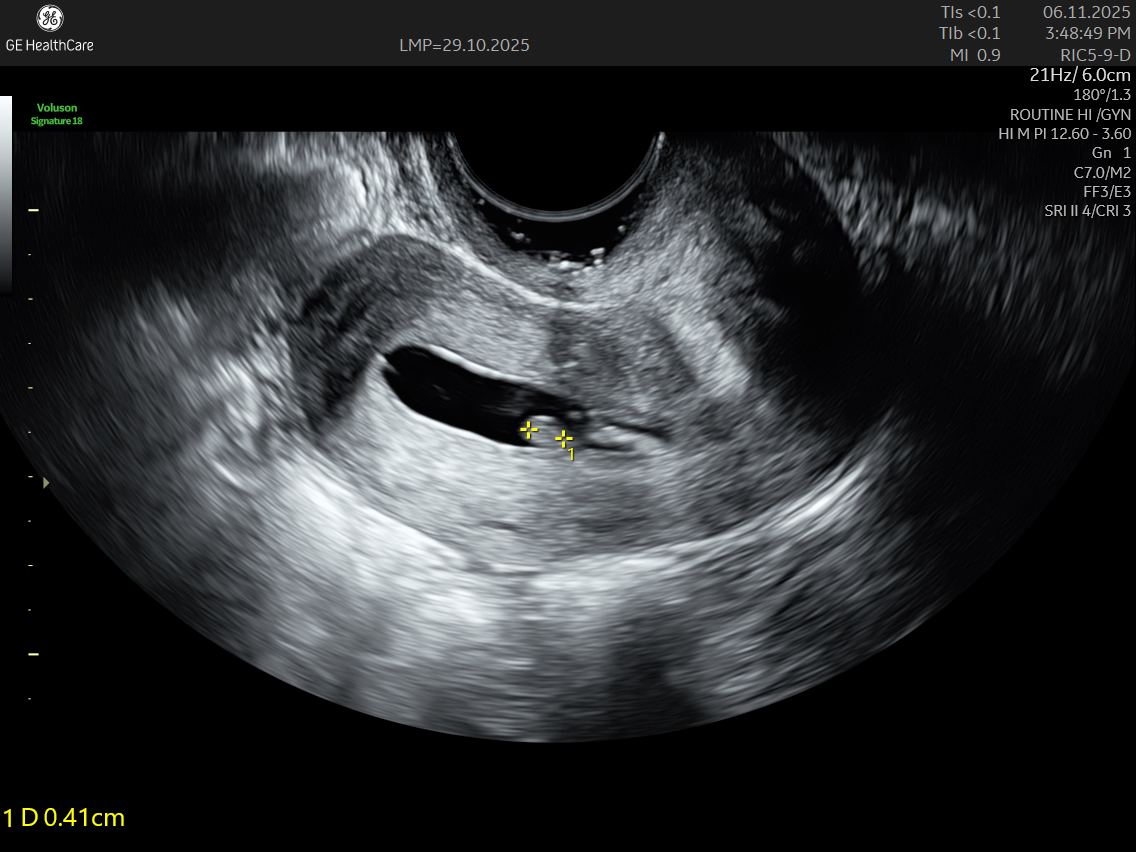

SIS is a diagnostic ultrasound technique designed to assess the uterus in greater detail. By filling the uterine cavity with a saline solution, the procedure separates the cavity walls and offers a clear contrast during imaging. This allows doctors to identify issues that might be missed on a standard pelvic ultrasound.

IMAGE GALLERY